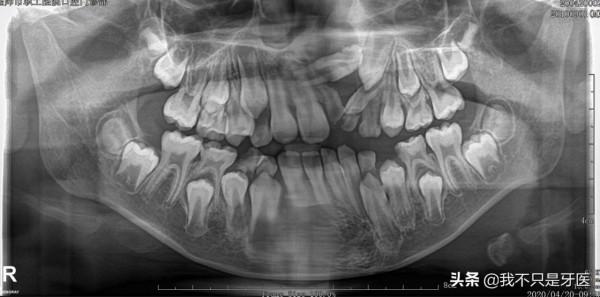

我看了看孩子口內的情況,右上門牙萌出,左上一顆畸形牙,初步診斷為“多生牙”。

我說:“給孩子拍一張曲面斷層片,更準確地確定多生牙的數目和方向,以及恆牙的位置。”

一張曲面斷層片,本可以早期發現問題,

觀察乳恆牙發育的整體狀況,瞭解牙齒數目,牙尖關係和牙齒替換狀況,同時把握乳牙根吸收程度,恆牙萌出方向及下頜骨情況,還可以用於記錄口腔頜面生長髮育狀況。

三、片子可以發現以下的問題:

1、多生牙,

2、先天缺牙,

3、牙齒形態是否異常,

4,、乳牙滯留、牙齒和牙槽骨是否粘連,

5,第一恆磨牙是否異位,

6、還有早期發現一些根尖囊腫,含牙囊腫等